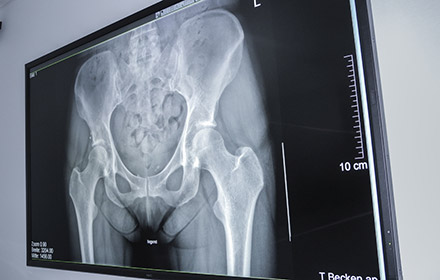

The Merian Iselin Hospital for Orthopaedics and Surgery is one of three large private hospitals in Basel, Switzerland and nationwide one of the houses with the largest number of surgical interventions in knee and hip surgery. The most important centre piece of the hospital is the radiology department, which creates imaging reports for both external and in-house physicians. More than 20,000 radiological examinations were carried out here in 2014.

The Merian Iselin Hospital selected the NEC MultiSync® X841UHD 8MP monitor featuring a screen diagonal of more than two metres and DICOM mode for clinical review of x-ray images for use in the MDT room. An NEC MultiSync MD322C8, with the same resolution as the large-format display, is used as an input monitor for the radiologists.

The extreme detail achieved with the UHD resolution display permits more precise diagnoses and allows extremely low viewing distances. Medical image data is reproduced correctly thanks to precise calibration and DICOM mode. “Black is really shown as black, just like white is really white on the screen”, says Dr. Egelhof with delight. A semi-matt surface restricts the effect of reflections on the screen.

“The Merian Iselin Hospital offers its customers and patients best service and highest quality. Therefore, the requirements which the hospital imposes on itself, also apply to the technical equipment”, says Christoph Kreutner, Technical and IT Manager of the hospital. “The discussion of the x-rays is now possible for the first time at the highest level, as the image can now be shown in the same quality and grade as on the diagnostic monitor.”